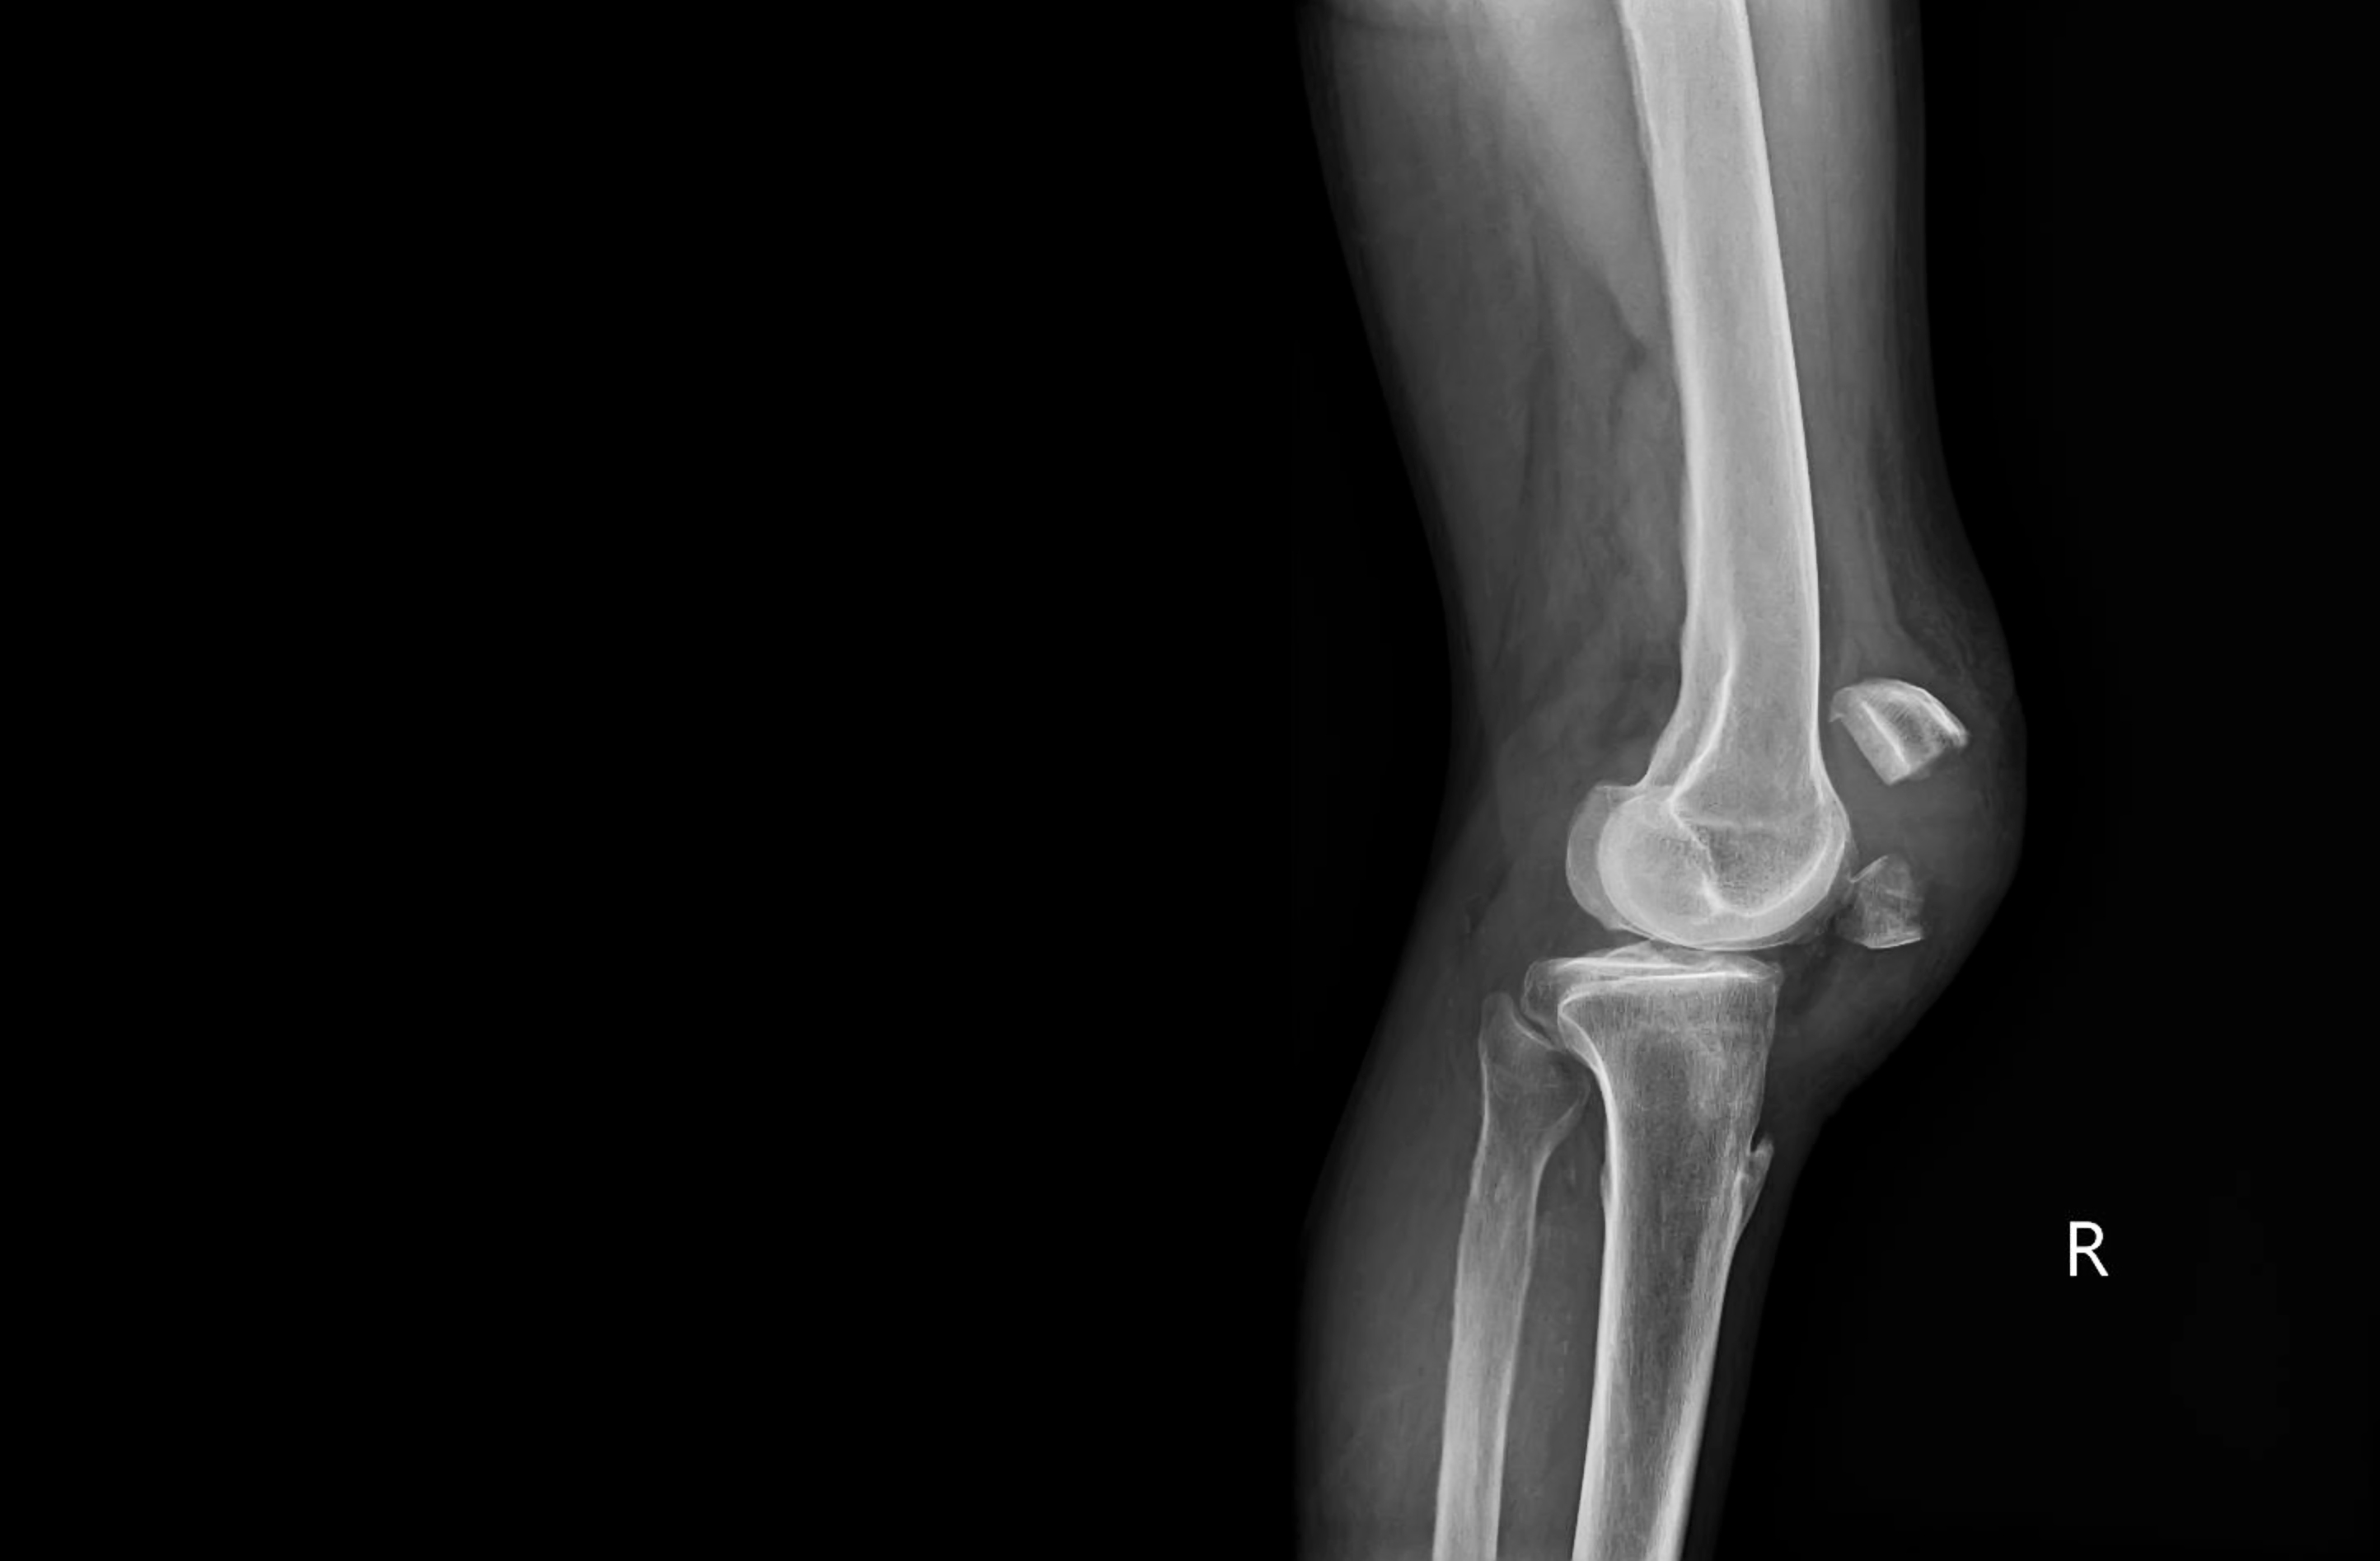

في جراحة الركبة، يركز على علاج حالات مثل التهاب المفاصل التنكسي للركبة، النخر، نقص التنسج، الركبة المتلاصقة، تبعات الكسور وعملية استئصال الغضروف الهلالي، بالإضافة إلى عمليات قطع العظم، وإصابات الأربطة أو الأوتار الباسطة، والأجسام الحرة داخل المفصل، والتكلس الغضروفي، والتهاب المفاصل والنقرس. يُجري عمليات استبدال الركبة الكلية بأسلوب طفيف التوغل، إلى جانب عمليات الاستبدال الجزئي للركبة وعمليات استبدال مفصل الرضفة. ومن خلال التنظير المفصلي، يقوم بعمليات استئصال الغضروف الهلالي وخياطته، وإعادة بناء الأربطة الصليبية الأمامية والخلفية والأربطة الجانبية، وكذلك إجراءات التقويم العظمي لتصحيح تشوهات الركبة الناتجة عن انحرافها نحو الداخل أو الخارج، وإعادة بناء الرباط الجناحي.